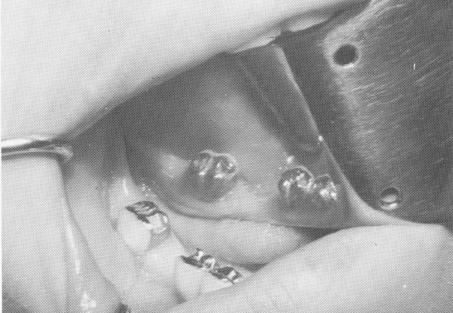

Fig. 8-76. Class II inlay preparations were prepared insid the gold work of the molar crown and second bicuspi crown.

2 Class II inlay gold preparations on posterior teeth, implant relevance